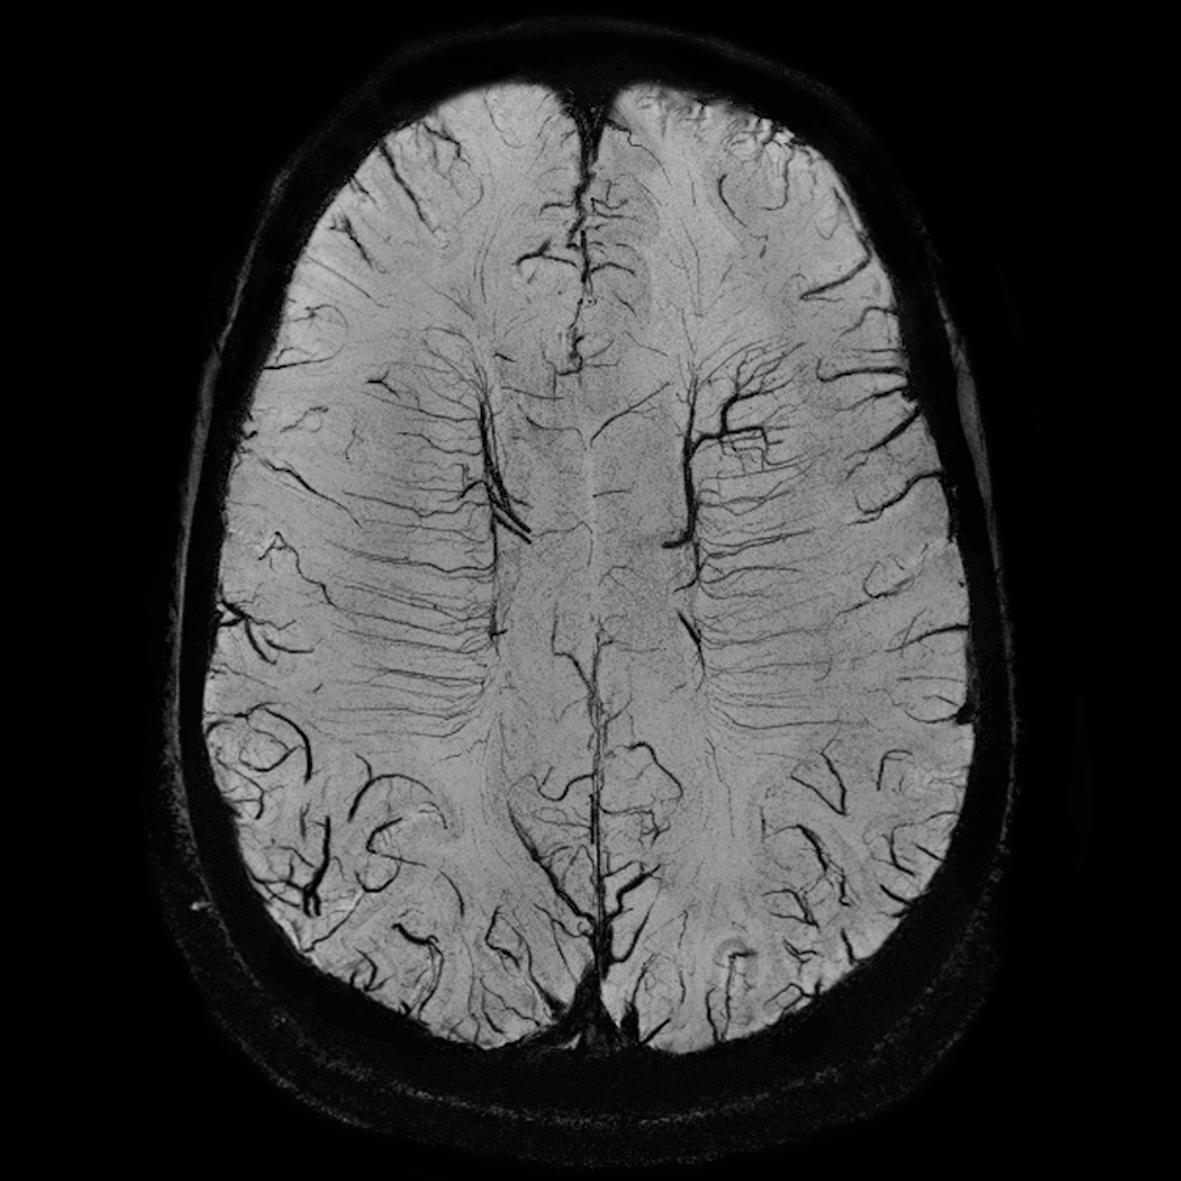

The progression to 7 Tesla (7 T) magnetic resonance imaging (MRI) yields promises of substantial increase in signaltonoise (SNR) ratio This increase can be traded off to increase image spatial resolution or to decrease acquisition time However, renal 7 T MRI remains challenging due to inhomogeneity of the radiofrequency field and due toThe Magentom Terra is the first 7T MRI system cleared for clinical use in the United States The spatial resolution of 7T MRI approaches the scale of pathologies of interest in degenerative brain diseases, such as amyloid plaques and changes in cortical layers and subcortical nuclei It may reveal new information about neurodegenerative dementias, although challenges may include increased artefact production and more adverse effects We performed a systematic

See other articles in PMC that citethe published article Abstract Magnetic resonance imaging and spectroscopy (MRI/MRS) at 7T represents an exciting advance in MR technology, with intriguing possibilities to enhance image spatial, spectral, and contrast resolution A comparison between 7T MRI and arthroscopy of the shoulder has been performed by LazikPalm et al , demonstrating the feasibility of clinical protocol acquisition at 7 T with diagnostic image quality in patients with suspected tendinopathy of the rotator cuff Compared to the arthroscopic evaluation, 7T MRI led to an overestimation of 7tesla (7T) MRI displays brain tissue characteristics more crisply than the 3T MRI that is in wide use today This advanced imaging technology, approved for clinical use by the FDA in 17 but used for research at Cleveland Clinic since 14, already is having a notable impact on the diagnosis and treatment of multiple sclerosis, epilepsy, traumatic brain injury, degenerative brain

The standard MRI brain imaging is done on 3T or similar MRI machine, but the 7T MRI machine has a larger magnet which has been shown to have superior resolution of the brain and of noncancerous brain lesions Diagnostic procedures such as 7T MRI may help find and diagnose melanoma brain metastases earlier than standard 3T MRIMAGNETOM Terra is the first 7T MRI scanner to unleash the full potential of the increased MR signal with multinuclear imaging and spectroscopy in clinical settings The multinuclear option allows the use of two dedicated coils in clinical mode – a 23 Na head coil and a 31 P loop coil, to explore metabolic insightsAt this time, our 7T MRI scanner is one of the most active in the United States and the Brain Behavior Laboratory and Lifespan Brain Institute are on the way to collecting one of largest datasets in healthy and abnormal development at 7T, allowing us to be leaders in brain research and move the field toward effective treatment and prevention